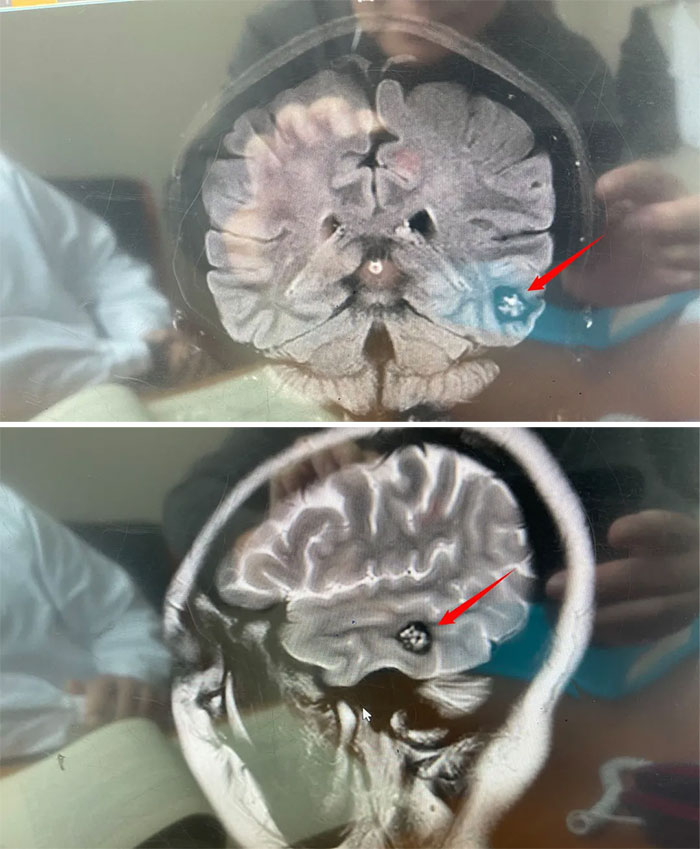

近期,頭痛進(jìn)行性加重,林女士去當(dāng)?shù)蒯t(yī)院就診,MRI檢查提示:左側(cè)顳葉凸面異常信號(hào)結(jié)節(jié)灶,提示海綿狀血管瘤可能性大,建議手術(shù)。經(jīng)慎重選擇,以及親友推薦,林女士來到了上海藍(lán)十字腦科醫(yī)院。

醫(yī)院神經(jīng)外科6A病區(qū)侯增欣主任團(tuán)隊(duì)為林女士完善相關(guān)檢查,頭顱磁共振顯示:左側(cè)顳葉見類圓形局灶性異常信號(hào)灶,約1.5*1.7*1.2cm。灶心“蜂窩狀”,灶內(nèi)微量出血(亞急性期)。

▲病灶灶心呈“蜂窩狀”